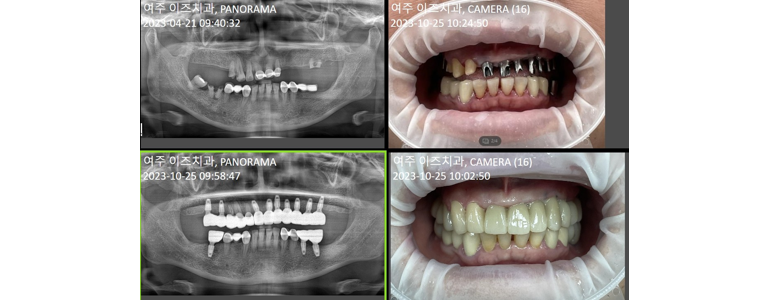

여주이즈치과의원

여주이즈치과의원은 경기도 여주시 세종로에 위치하며, 여주시청별관 2층 에 있어 접근성이 뛰어납니다. 첨단 CT 장비를 완비해 정밀한 진단과 당일 임플란트 시술이 가능하며, 매랑니 발치 와 보험 틀니 시술도 전문적으로 진행합니다. 믿을 수 있는 진료로 지역 주민에게 꾸준히 사랑받고 있습니다.

상호명 안내 : 여주이즈치과의원

고객센터 : 031-881-2897

선택 이유 : 첨단 CT 활용 정밀진료, 당일 임플란트 시술 가능, 매랑니 안전 발치, 보험 틀니 지원

위치 정보 : 경기 여주시 세종로 10 영무빌딩 201호 (여주시청별관 건물 2층)